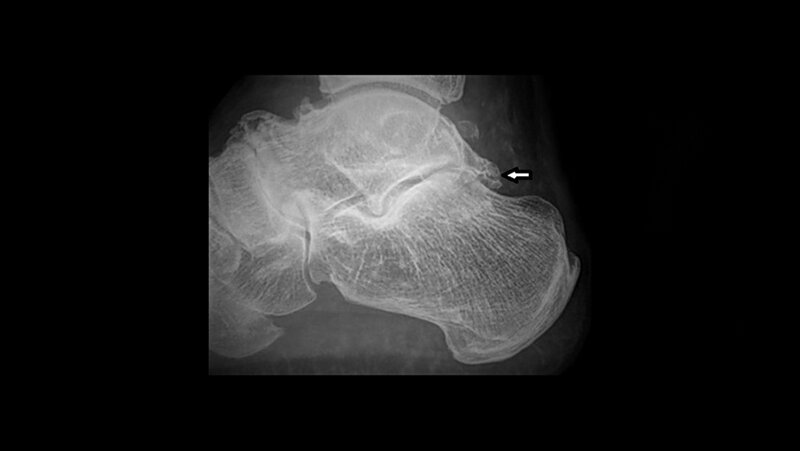

Das Os trigonum ist ein akzessorisches Knöchelchen des Talus und ein häufiger radiografischer Befund. In 70 % der Fälle erfolgt eine knöcherne Fusion bis zum 17. Lebensjahr. Das Os-trigonum-Syndrom ist das Resultat einer Überbeanspruchung der hinteren Knöchelregion, verursacht durch wiederholte Plantarflexionen. Es ist oft mit pathologischen Veränderungen der Flexor-hallucis- longus Sehne vergesellschaftet.

Os trigonum is an accessory ossicle of the talus and is a common radiographic finding. 70 % of subjects with os trigonum achieved fusion by the age of 17. Os trigonum syndrome is the result of an overuse of the posterior ankle caused by repetitive plantar flexion stress. It is often associated with pathology of the flexor hallucis longus tendon.